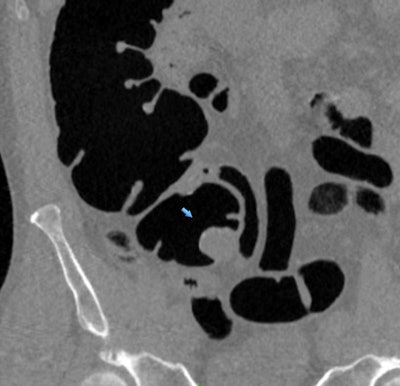

Believing that ample data already existed that simply needed to be aggregated and analyzed, Pickhardt and colleagues examined the results of 34 studies published between January 1994 and August 2017 that included 18,798 seniors who underwent CTC screening for colorectal cancer. CTC's positive screening rates for large polyps or cancers ranged from 9% to 31%, with a sensitivity of 93%, and it had a positive predictive value of 84.3% for advanced colorectal cancer (AJR, April 18, 2018).